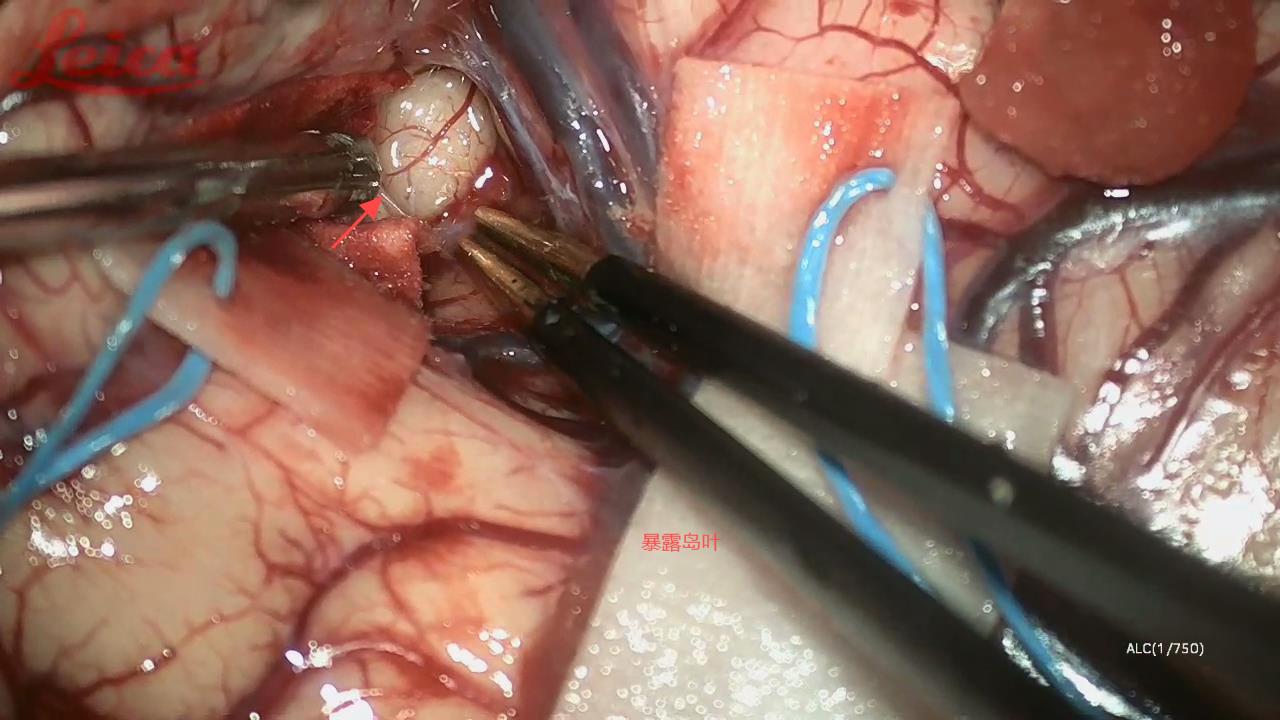

经外侧裂-岛叶造瘘清除血肿简要

经外侧裂-岛叶造瘘清除基底节出血